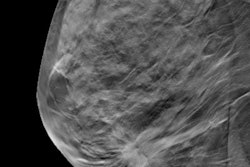

A host of recent studies have set out to compare the pros and cons of digital breast tomosynthesis (DBT) and digital mammography for screening, but very few researchers have looked specifically at the financial aspects.

Norwegian investigators have tried to fill this void by scrutinizing the costs of screening nearly 30,000 women using these two techniques. Go to the Women's Imaging Community.